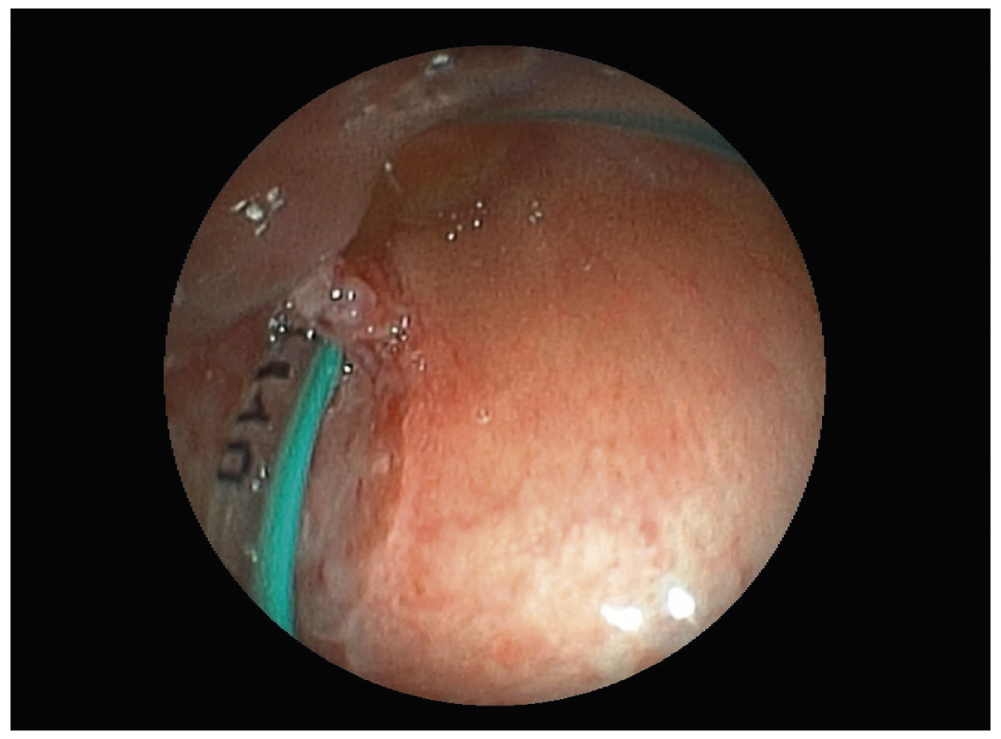

Если задренировать желудок не удавалось, то выполняли фиброэзофагоскопию ультратонким эндоскопом, при которой в ряде случаев возможно было не только оценить локализацию и размеры дефекта стенки пищевода, но и ввести зонд в желудок под эндоскопическим контролем (рис. 6, 7).

Рис. 6. Эзофагоскопия: желудочный зонд установлен через левый грушевидный синус; видна интубационная трубка в просвете гортани

Fig. 6. Esophagoscopy: nasogastric tube has been inserted through the left pyriform sinus (the intubation tube can be seen in the laryngeal lumen)

Рис. 7. Эзофагоскопия: желудочный зонд установлен в просвет пищевода под эндоскопическим контролем; виден дефект в области левого грушевидного синуса

Fig. 7. Esophagoscopy: nasogastric tube has been inserted into the esophageal lumen has been performed under endoscopic guidance. A left pyriform sinus defect is now clearly visible